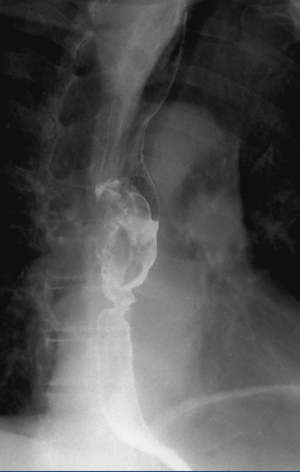

Рентгенография пищевода с бариевой взвесью/водорастворимым контрастным препаратом